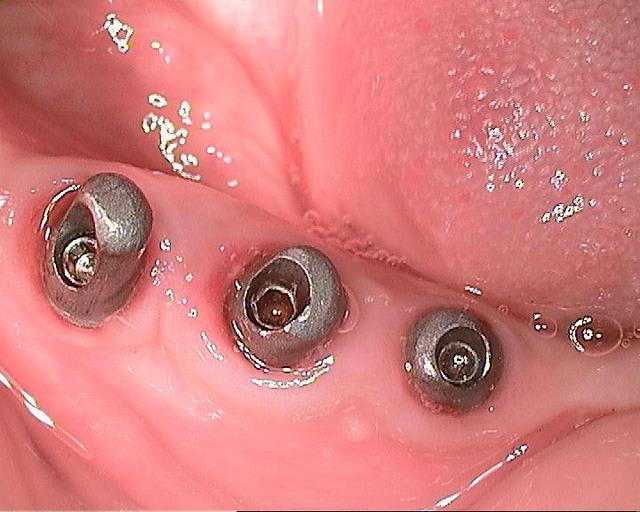

des photos d'un cas d'aujourd'hui avec le shuttle retiré ( 8 premières photos)

les 4 dernières c'est avec le foret , la dernière photo c'est un cas d'extraction implantation d'aujourd'hui aussi on voit la nouvelle alvéole après le forage ( désolé pour la qualité de photo...)